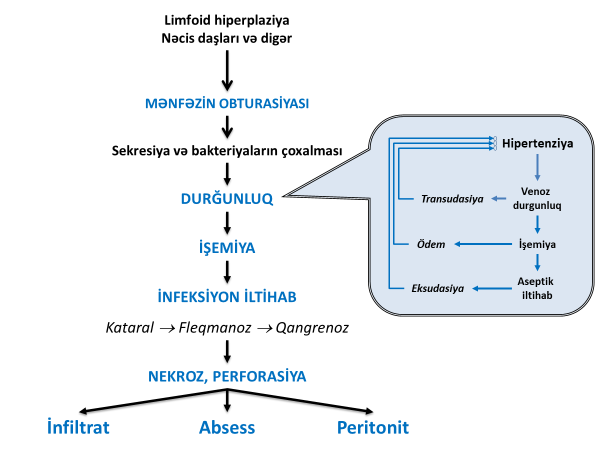

Kəskin appendisitin baş verməsində və gedişində əsas mexanızm mənfəzdaxili hipertenziya və divar işemiyasıdır.

Obturasiya nəticəsində çıxıntının mənfəzində meydana gələn durğunluq seliyin toplanmasına və bakteriyaların inkişafına səbəb olur. Bunlar mənfəzdaxili təzyiqin artmasına gətirib çıxarır. Hipertenziya divarda işemiya və aseptik iltihaba səbəb olur. Aseptik iltihaba bağırsaq infeksiyalarının qoşulması (Escherichia coli, Peptostreptococcus, Bacteriodes, Pseudomonans və s) iltihabi prosesi ağırlaşdırır.

İlk 6-12 saat ərzində iltihab mukozanı əhatə edir (kataral appendisit), 12-24 saat ərzində bütün qatları əhatə edən irinli iltihab (fleqmanoz appendisit), 24-48 saat sonra isə nekroz və perforasiyalar (qanqrenoz appendisit) meydana gəlir (Şəkil 1).

Şəkil 1.Appendisitin patogenezi